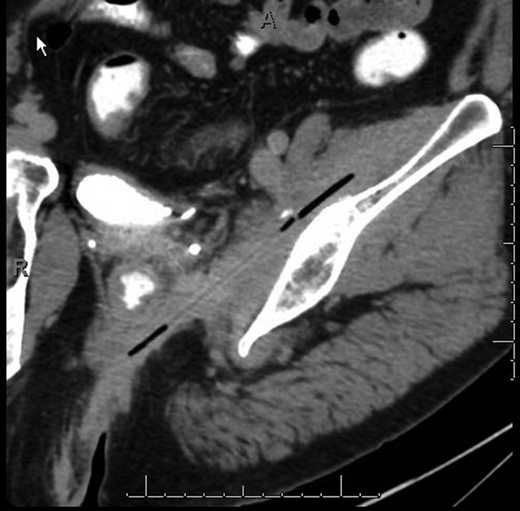

Two months after the initial presentation, the patient returned to the ED for the fourth time complaining of left hip pain. The buttock wound was examined and found to track inward roughly five inches, prompting a CT scan. The imaging showed a linear, partially gas-filled tract starting dorsal to the distal rectum and extending obliquely cephalad and leftward through the obturator internus and iliopsoas musculature (Fig. 1). Soft tissue thickening, mild edema and heterogeneous enhancement were noticed surrounding the tract, but no connection to the rectum or anus was seen.

CT image of a linear, partially gas-filled tract starting dorsal to the distal rectum and extending obliquely cephalad and leftward through the obturator internus and iliopsoas musculature.